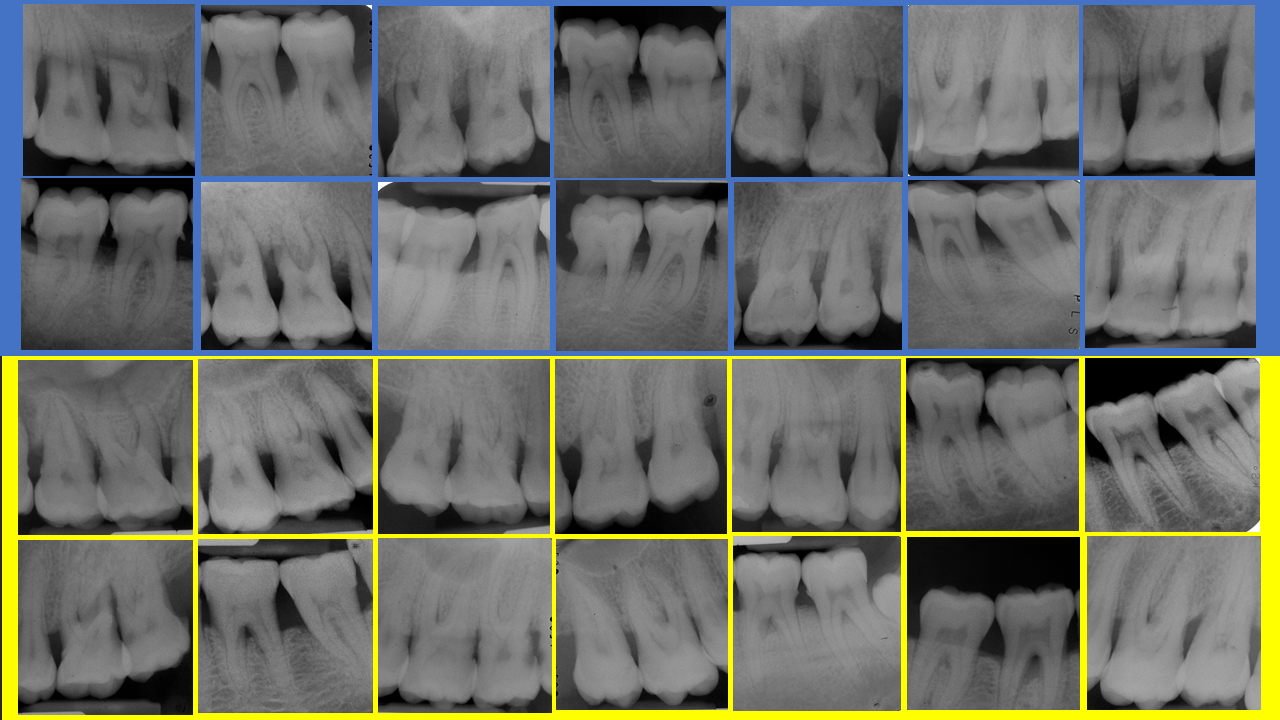

More than 65,000 data analysed on 500 patients over 25 years

This predictive model´s database is one of the largest samples to monitor tooth loss due to periodontal disease in patients following periodontal maintenance (Martinez-Canut, P. (2015) Predictors for tooth loss due to periodontal disease in patients following long-term periodontal maintenance. Journal of Clinical Periodontology 42, 1115-1125).

About twenty factors predictive of tooth loss were analysed using different statistical tests, searching for consistency of results. Eleven of these factors, most clearly associated with tooth loss, were finally selected to construct the predictive model.